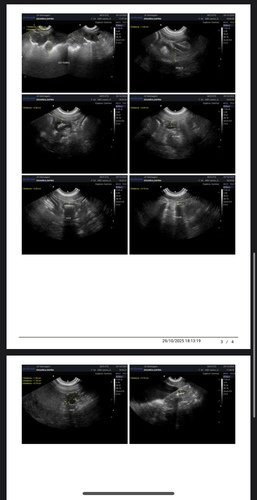

Alguns meses atrás realizamos exames e biópsia que teve como resultado hemangioma, um tumor benigno que poderia virar um tumor maligno chamado emangiossarcoma. Como são vários nódulos pelo corpo dela, existia chance de algum deles já ser maligno. Então nossa saída era fazer outros exames para poder começar uma eletroquímio, porém na ultrassom encontramos uma neoplasia de 14cm na parede do estômago, cisto no ovário esquerdo e pancreatite.

Já fizemos a gastrectomia para biópsia e castração, para agora acompanhar com ultrassom. Para um cachorro de grande porte e uma cirurgia delicada, o custo que já era alto ficou ainda maior. Felizmente está tudo correndo bem, ela está ótima para alguém que operou. Hoje, clinicamente ela está bem e não apresenta nenhum sintoma, então é o melhor momento para tratar a cuidar dela. Estamos com um veterinário de muita confiança para observar cada mudança com ela e aplicar vitaminas que são importantes para o imunológico dela. Mas ainda temos que terminar de pagar os custos dessa primeira primeira parte que passamos. Não pretendemos atingir metas, mas qualquer ajuda será recebida com muita gratidão! Se começarmos temos que ir até o final, pelo bem e carinho que temos por ela. Toda ajuda é bem vinda!